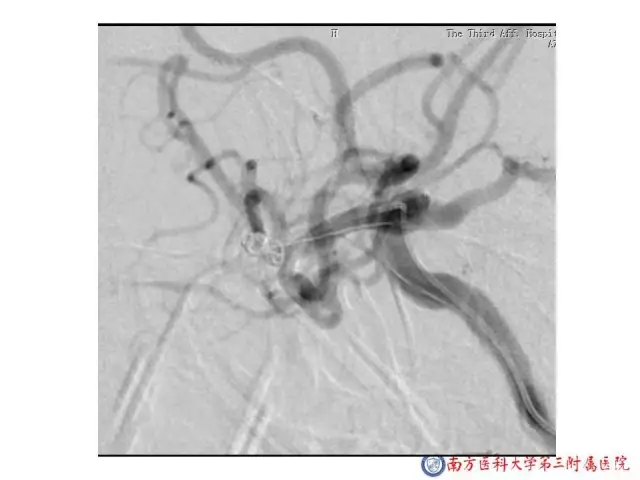

今天为大家分享的是“强生医疗CNV-神经介入专栏”第二十五期,由南方医科大学第三附属医院神经外科主任黄理金教授带来的“Enterprise支架辅助栓塞动脉瘤的优势”精彩讲课视频及PPT,欢迎观看。文章仅代表作者个人观点,如有不同见解,欢迎同道斧正!